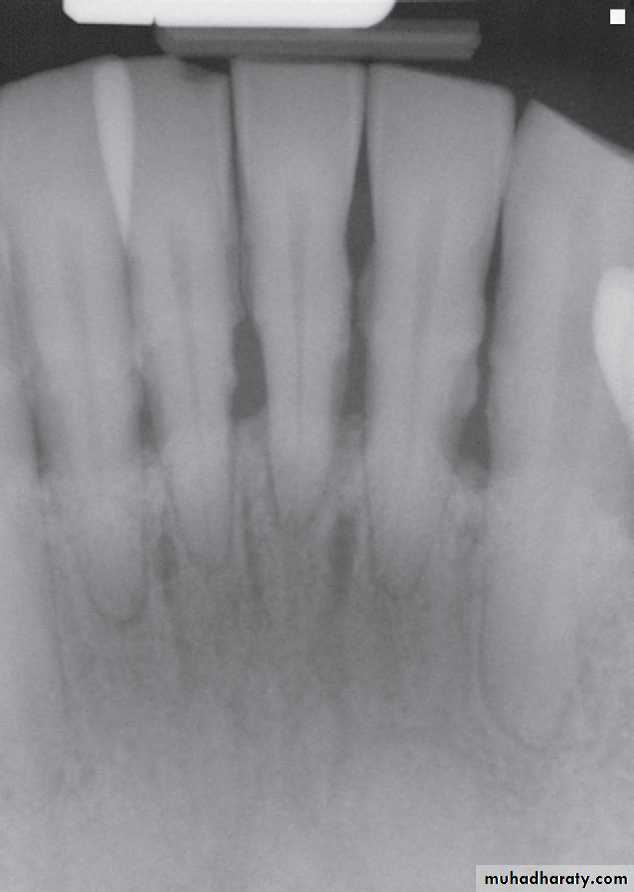

horizontal bone loss:

Bone loss occurs in a plane parallel to CEJs of adjacent teeth.

Horizontal bone lossis used to describe the radiographic appearance of the loss of bone height in the region of several adjacent teeth. Horizontal bone loss may be classified as localized or generalized, depending on the regions involved.

vertical (angular) bone loss:

Bone loss doesn’t occur in plane parallel to CEJs of adjacent teeth.Vertical bone loss

Vertical bone defects-are also called proximal intrabony defects. The defect extends apically2- Distribution